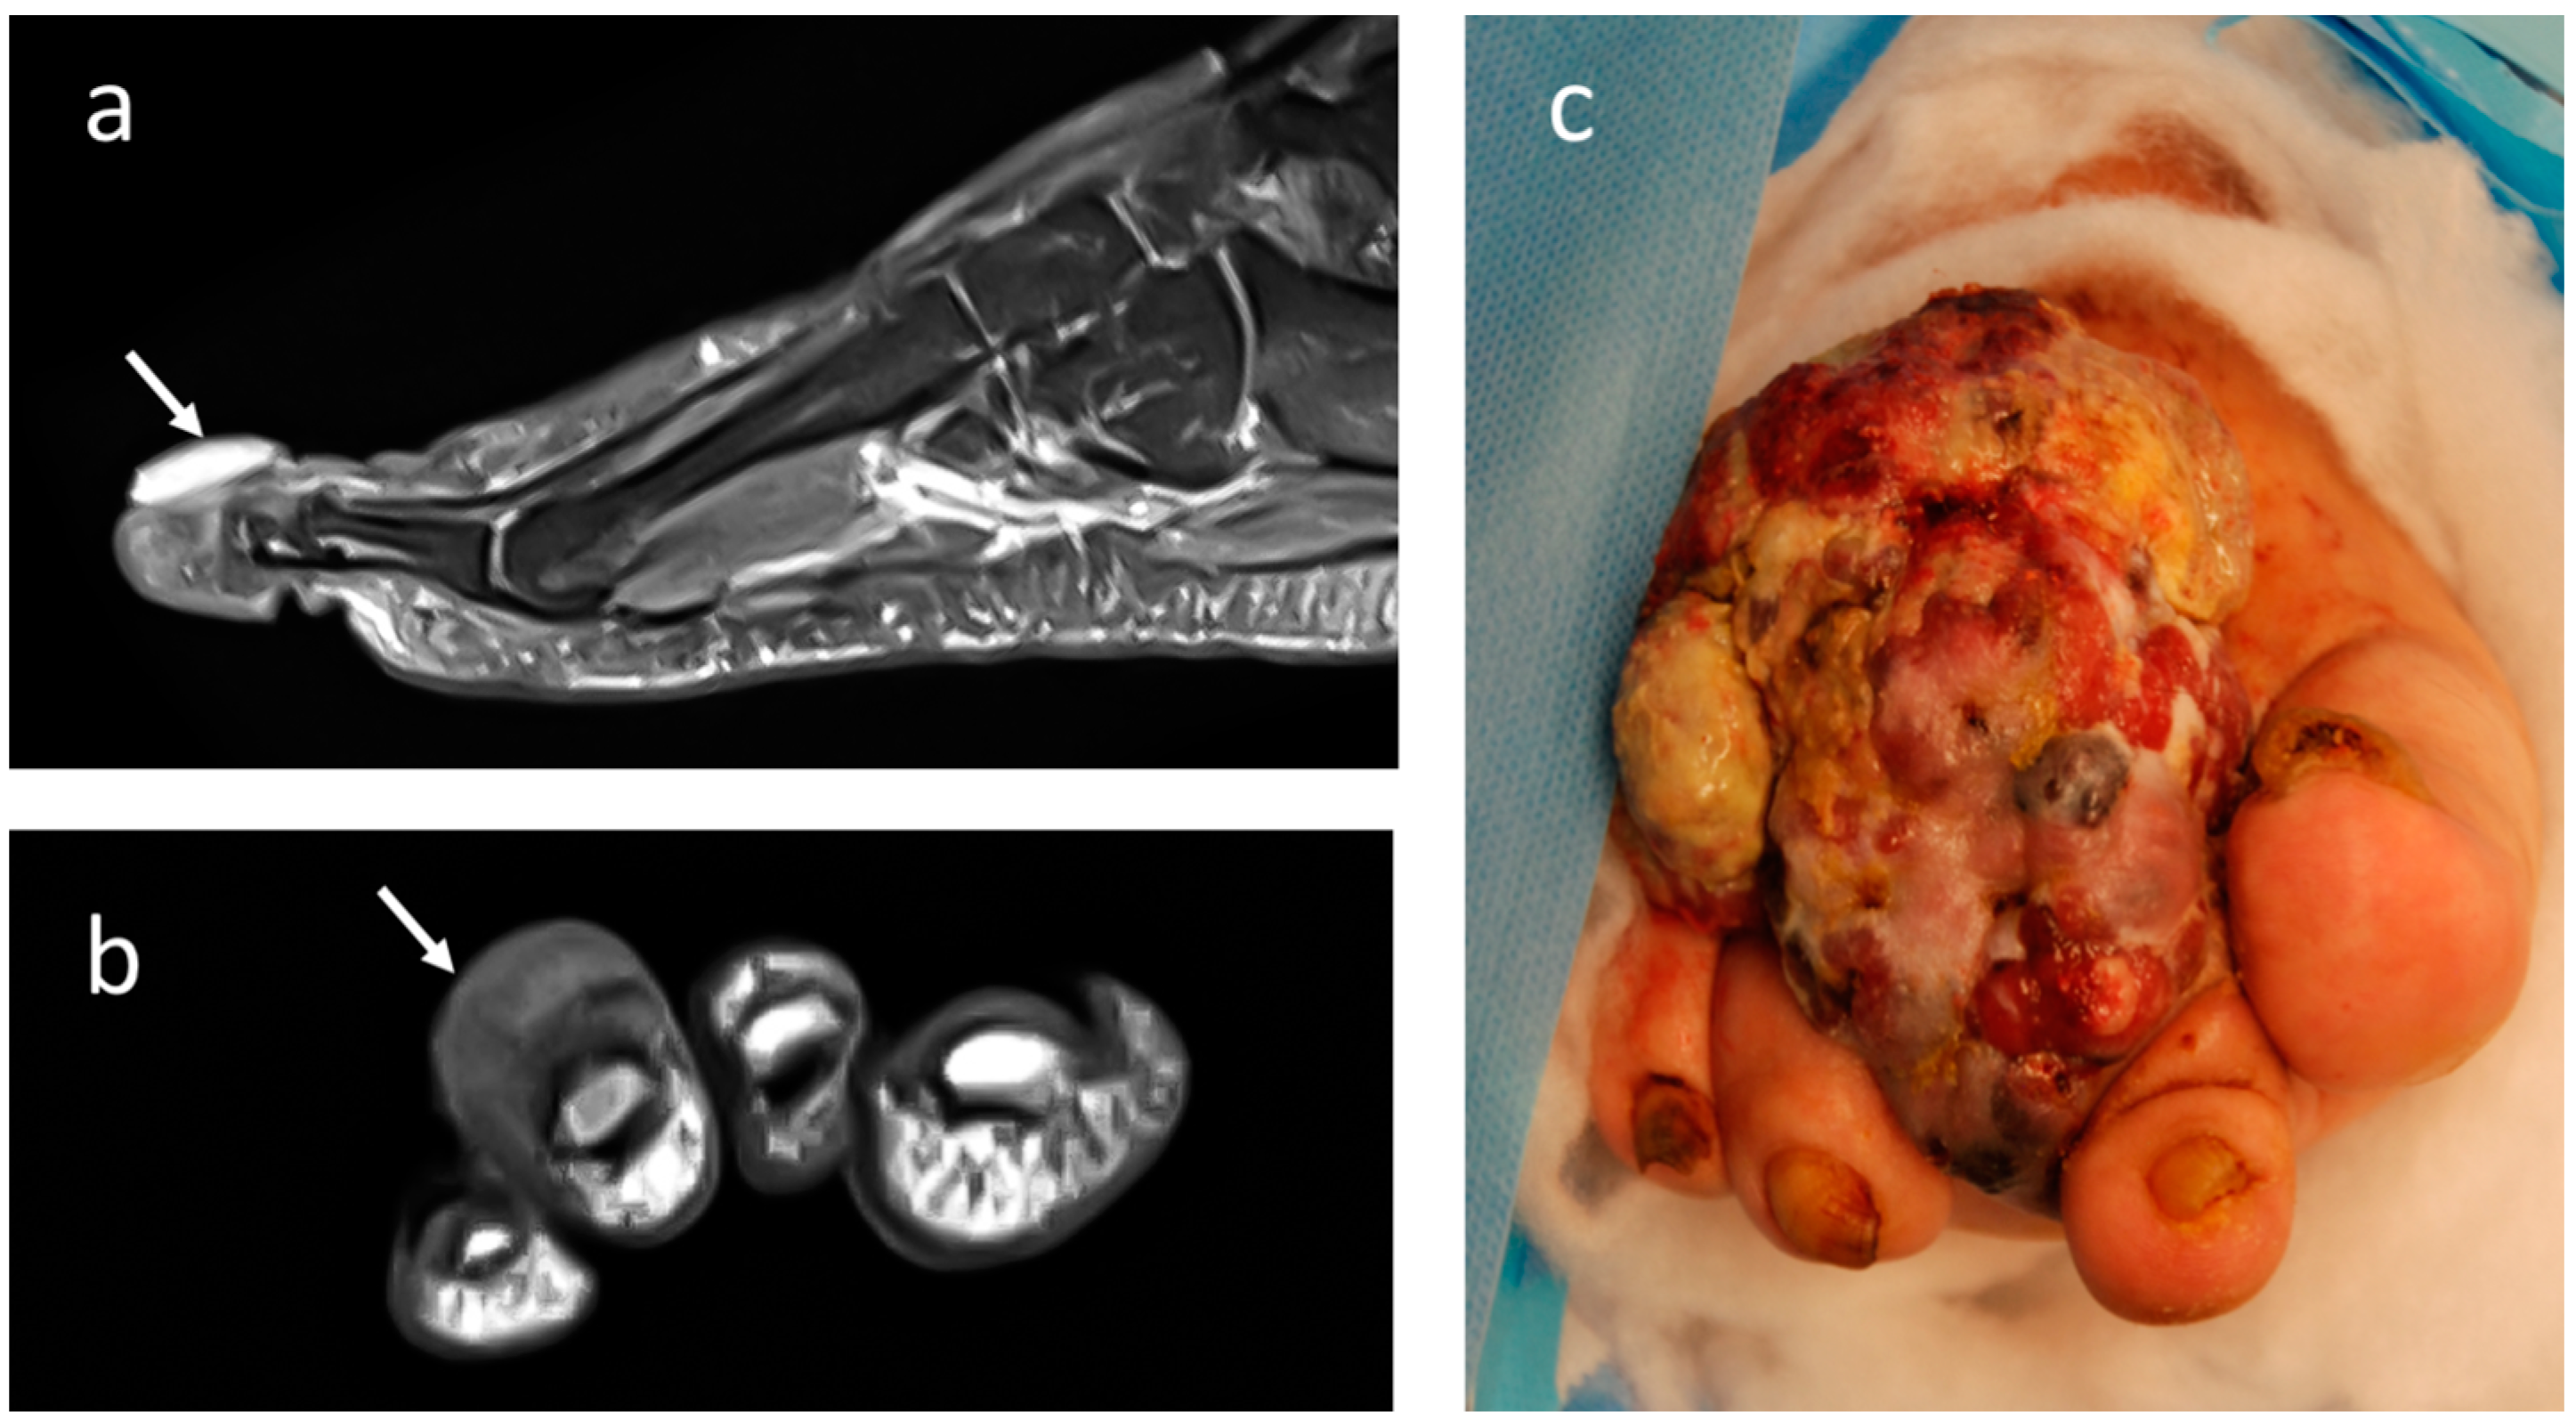

4.1. Melanoma

4.2. Epithelioid Sarcoma